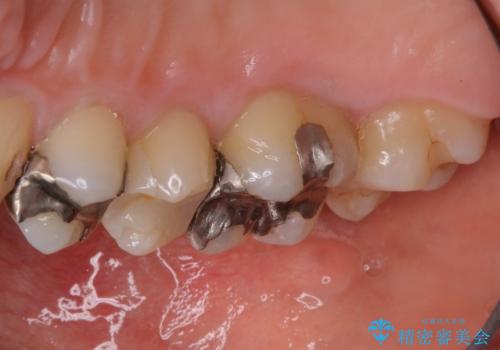

- クラウンやインレー等の補綴物には効果がありません